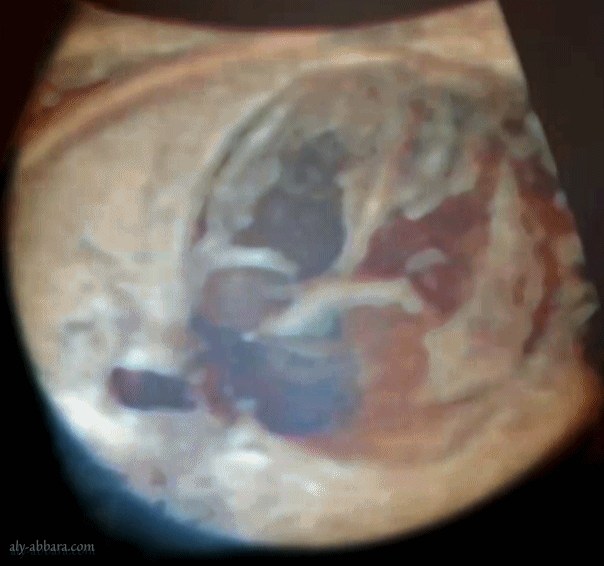

Artère ombilicale unique - grossesse de 33 SA - Absence de d'anomalie associée

Cœur fœtal à 33 SA : coupe des quatre cavités

Technique : vidéo avec activation de la fonction light, mais ce vidéo résulte de traitement-vidéo par ordinateur.

Sur cette vidéo on observe parfaitement les quatre cavités cardiaques : OG (oreillette gauche) ; VM (valve mitrale) ; VG (ventricule gauche) ; OD (oreillette droite) ; VTC (valve tricuspide) ; VD (ventricule droit) ; FO (foramen ovale) et l'aorte descendante.